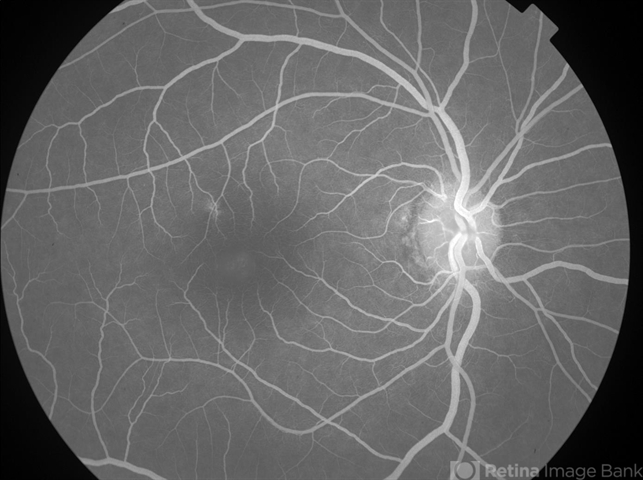

- Pseudocystic Foveal Cavitation in Tamoxifen Retinopathy

- tamoxifen maculopathy, tamoxifen retinopathy, tamoxifen toxicity, pseudocystic foveal cavitiation, foveal cavitation

- 50-year-old female with breast cancer referred for CME had noticed gradual decrease in vision over the last 6-12 months; pseudocystic foveal cavitation due to tamoxifen retinopathy diagnosed by Dr. Hruby. Visual acuity cc 20/360, J16 OD and 20/40, J7 OS, normal IOPs, trace NSC OU. Bilateral pseudoholes noted on posterior segment exam without any retinal crystals. No leakage or tel vessels seen on the FA. Cystic cavitary alterations seen on the OCT with a large outer hole in the left eye. Plaquenil will be d/c.